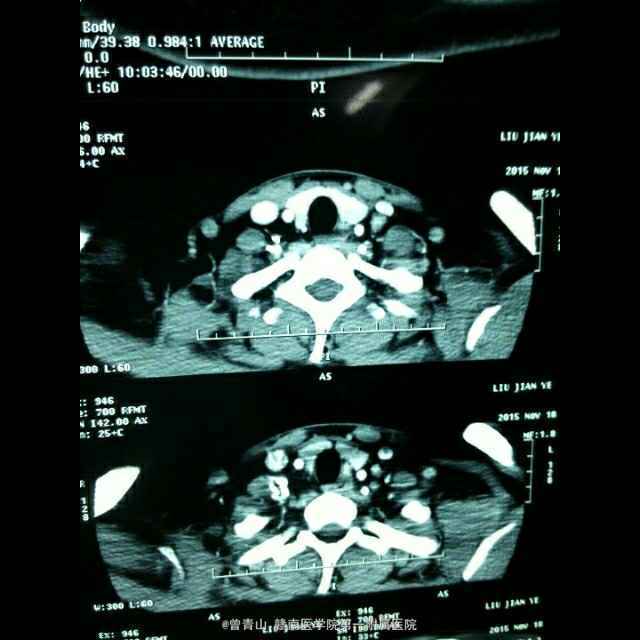

患者男性,20岁,因“咽部不适20天,发现颈部包块1天入院” 患者因咽部不适,吞咽异物感就诊于当地医院,一直给予针对慢性咽喉炎治疗,无明显效果。患者于昨日就诊于我科门诊,查体发现左侧甲状腺肿大,给予彩超检查发现左侧甲状腺肿物。

查体:心肺腹未见异常,口腔面膜充血,咽部见淋巴滤泡。甲状腺触诊发现左侧Ⅱ度肿大,边界不清,活动度尚可。 CT,彩超

诊断:甲状腺癌、慢性咽喉炎 治疗:手术方式~甲状腺左侧腺叶+峡部切除+喉返神经解剖术+中央区淋巴结清扫

术后病理示甲状腺乳头状癌,未见淋巴结转移 甲状腺癌手术范围选择,一直都不是很清楚。望各位同仁指点!